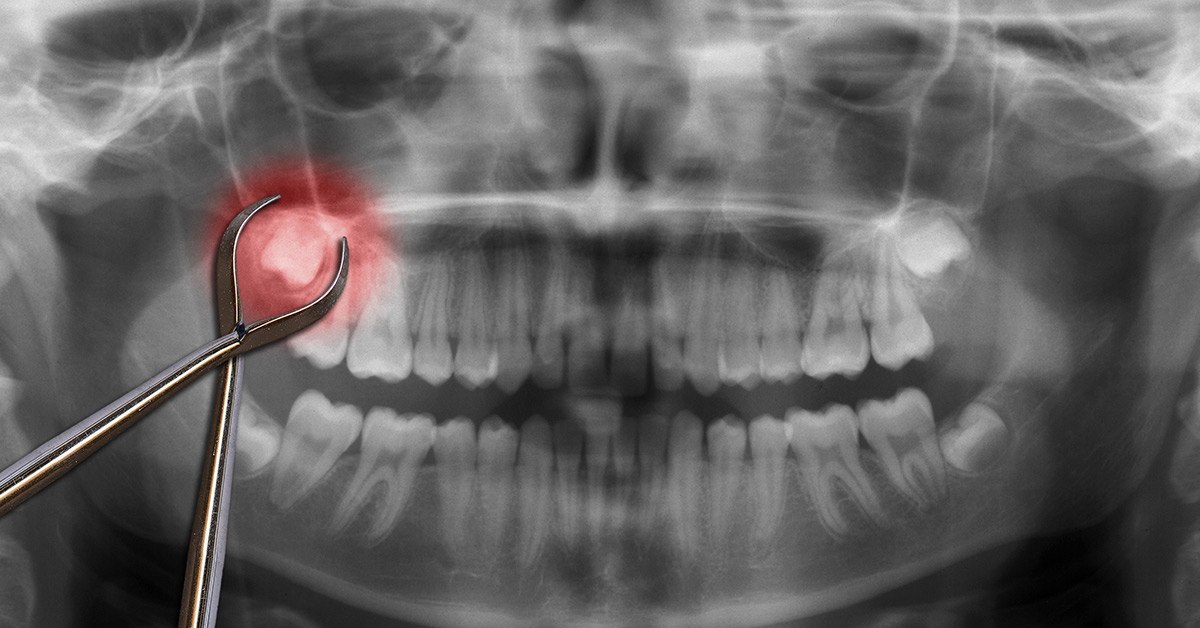

Denumirea medicala pentru o masea de minte este molarul 3, fiind dintele cel mai indepartat de pe arcada dentara. Apare cel mai tarziu, cand maxilarul si arcadele dentare s-au dezvoltat complet. Daca eruptia nu poate avea loc din cauza lipsei spatiului, sau apar inghesuiri, sau compromite sanatatea molarilor vecini, medicul stomatolog va recomanda extragerea sa, pentru a evita complicatii stomatologice ulterioare.

Principalul motiv pentru care oamenii opteaza sa-si extraga maselele de minte este felul in care acestea cresc (intr-un unghi dificil), ceea ce poate provoca disconfort sau probleme stomatologice mai serioase. In alte cazuri, din cauza spatiului ingust, maseaua de minte poate sa creasca doar pe jumatate sau mai putin, aglomerand alinierea dintilor.

Molarii de minte pot avea radacini atipice, deseori ramanand blocati in spatele celui de-al doilea moalar (incluzie).

Medicul stomatolog este cel care iti poate recomanda scoaterea maselei de minte, in urma unui examen clinic si a efecturii unei radiografii, pe baza careia medicul poate sa vada starea maselei de minte in os si gingie (in cazurile in care exista).